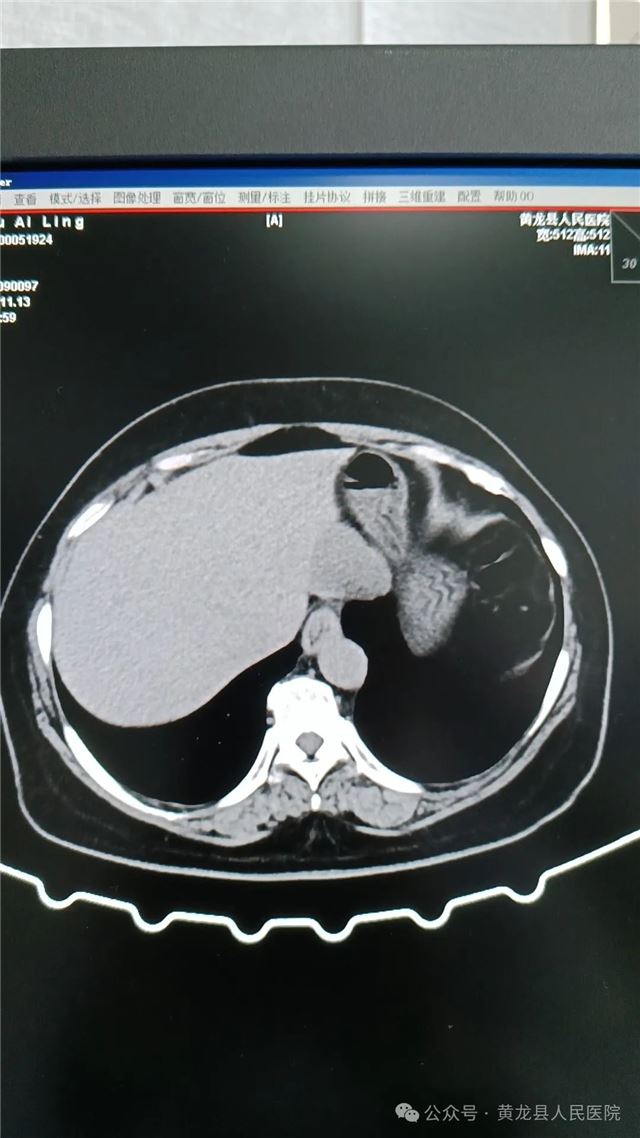

1,术前上腹部CT(平扫、增强)

患者女,58岁,在体检时发现肝占位性病变,经进一步检查后确诊“肝血管瘤”。